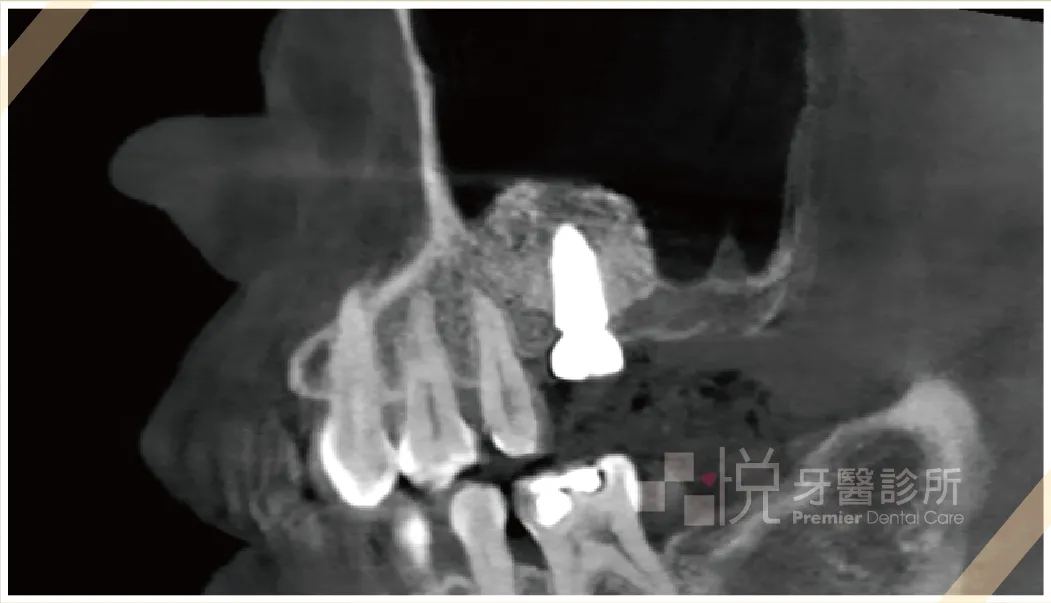

➊由於剩餘骨頭高度剩約 1mm 嚴重不足,醫師決定先進行鼻竇增高術,半年後再植入植體。

➍ 側方開窗法術後x光確認術後結果,有顆粒感的白色部分為放入置骨粉,原本 1mm 提升至12mm。

➎ 術後 X 光片顯示,鼻竇膜被安全剝離,並成功填塞骨粉,等待骨頭成長後再植入植體。